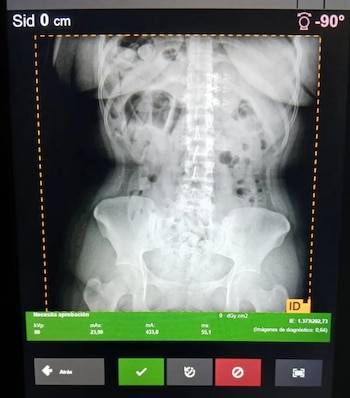

Las pasajeras de procedencia boliviana presentaban molestias abdominales durante la inspección de rutina y dispusieron su traslado primero al Hospital de Trancas para estudios radiográficos. La acción fue ordenada ante las sospechas de los efectivos de la Patrulla Eventual “Trancas”, dependiente del Escuadrón 55 “Tucumán” por un posible delito vinculado al narcotráfico.

El protocolo de emergencia se activó cuando la pasajera presentó un cuadro de dolor abdominal y desorientación, síntomas que alertaron a los uniformados sobre la posibilidad de ingesta de estupefacientes, modalidad que implica un riesgo letal si alguna cápsula se rompe. La mujer fue trasladada de inmediato al Hospital San Juan Bautista, donde estudios radiológicos confirmaron la presencia de cuerpos extraños en su tracto digestivo.